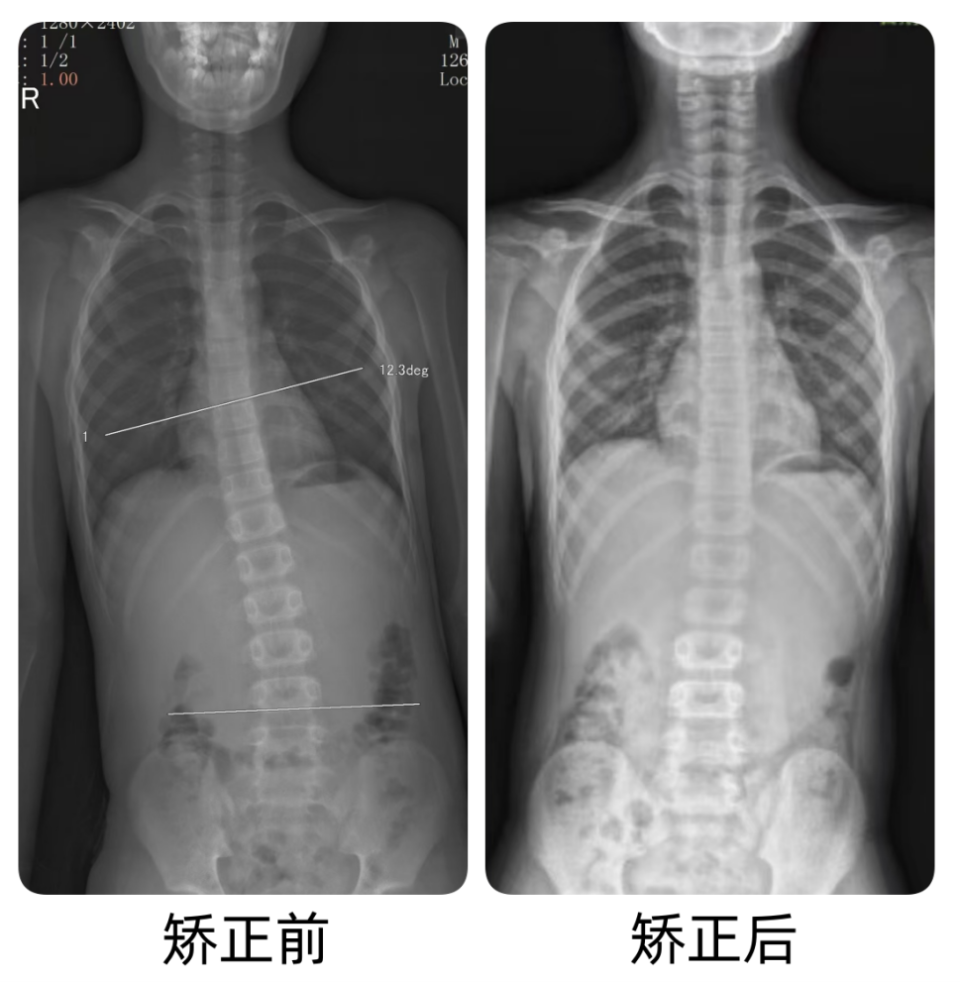

分享一例青少年重度脊柱侧弯案例,患者2年前发现侧弯,当时就有

15岁女孩,脊柱侧弯